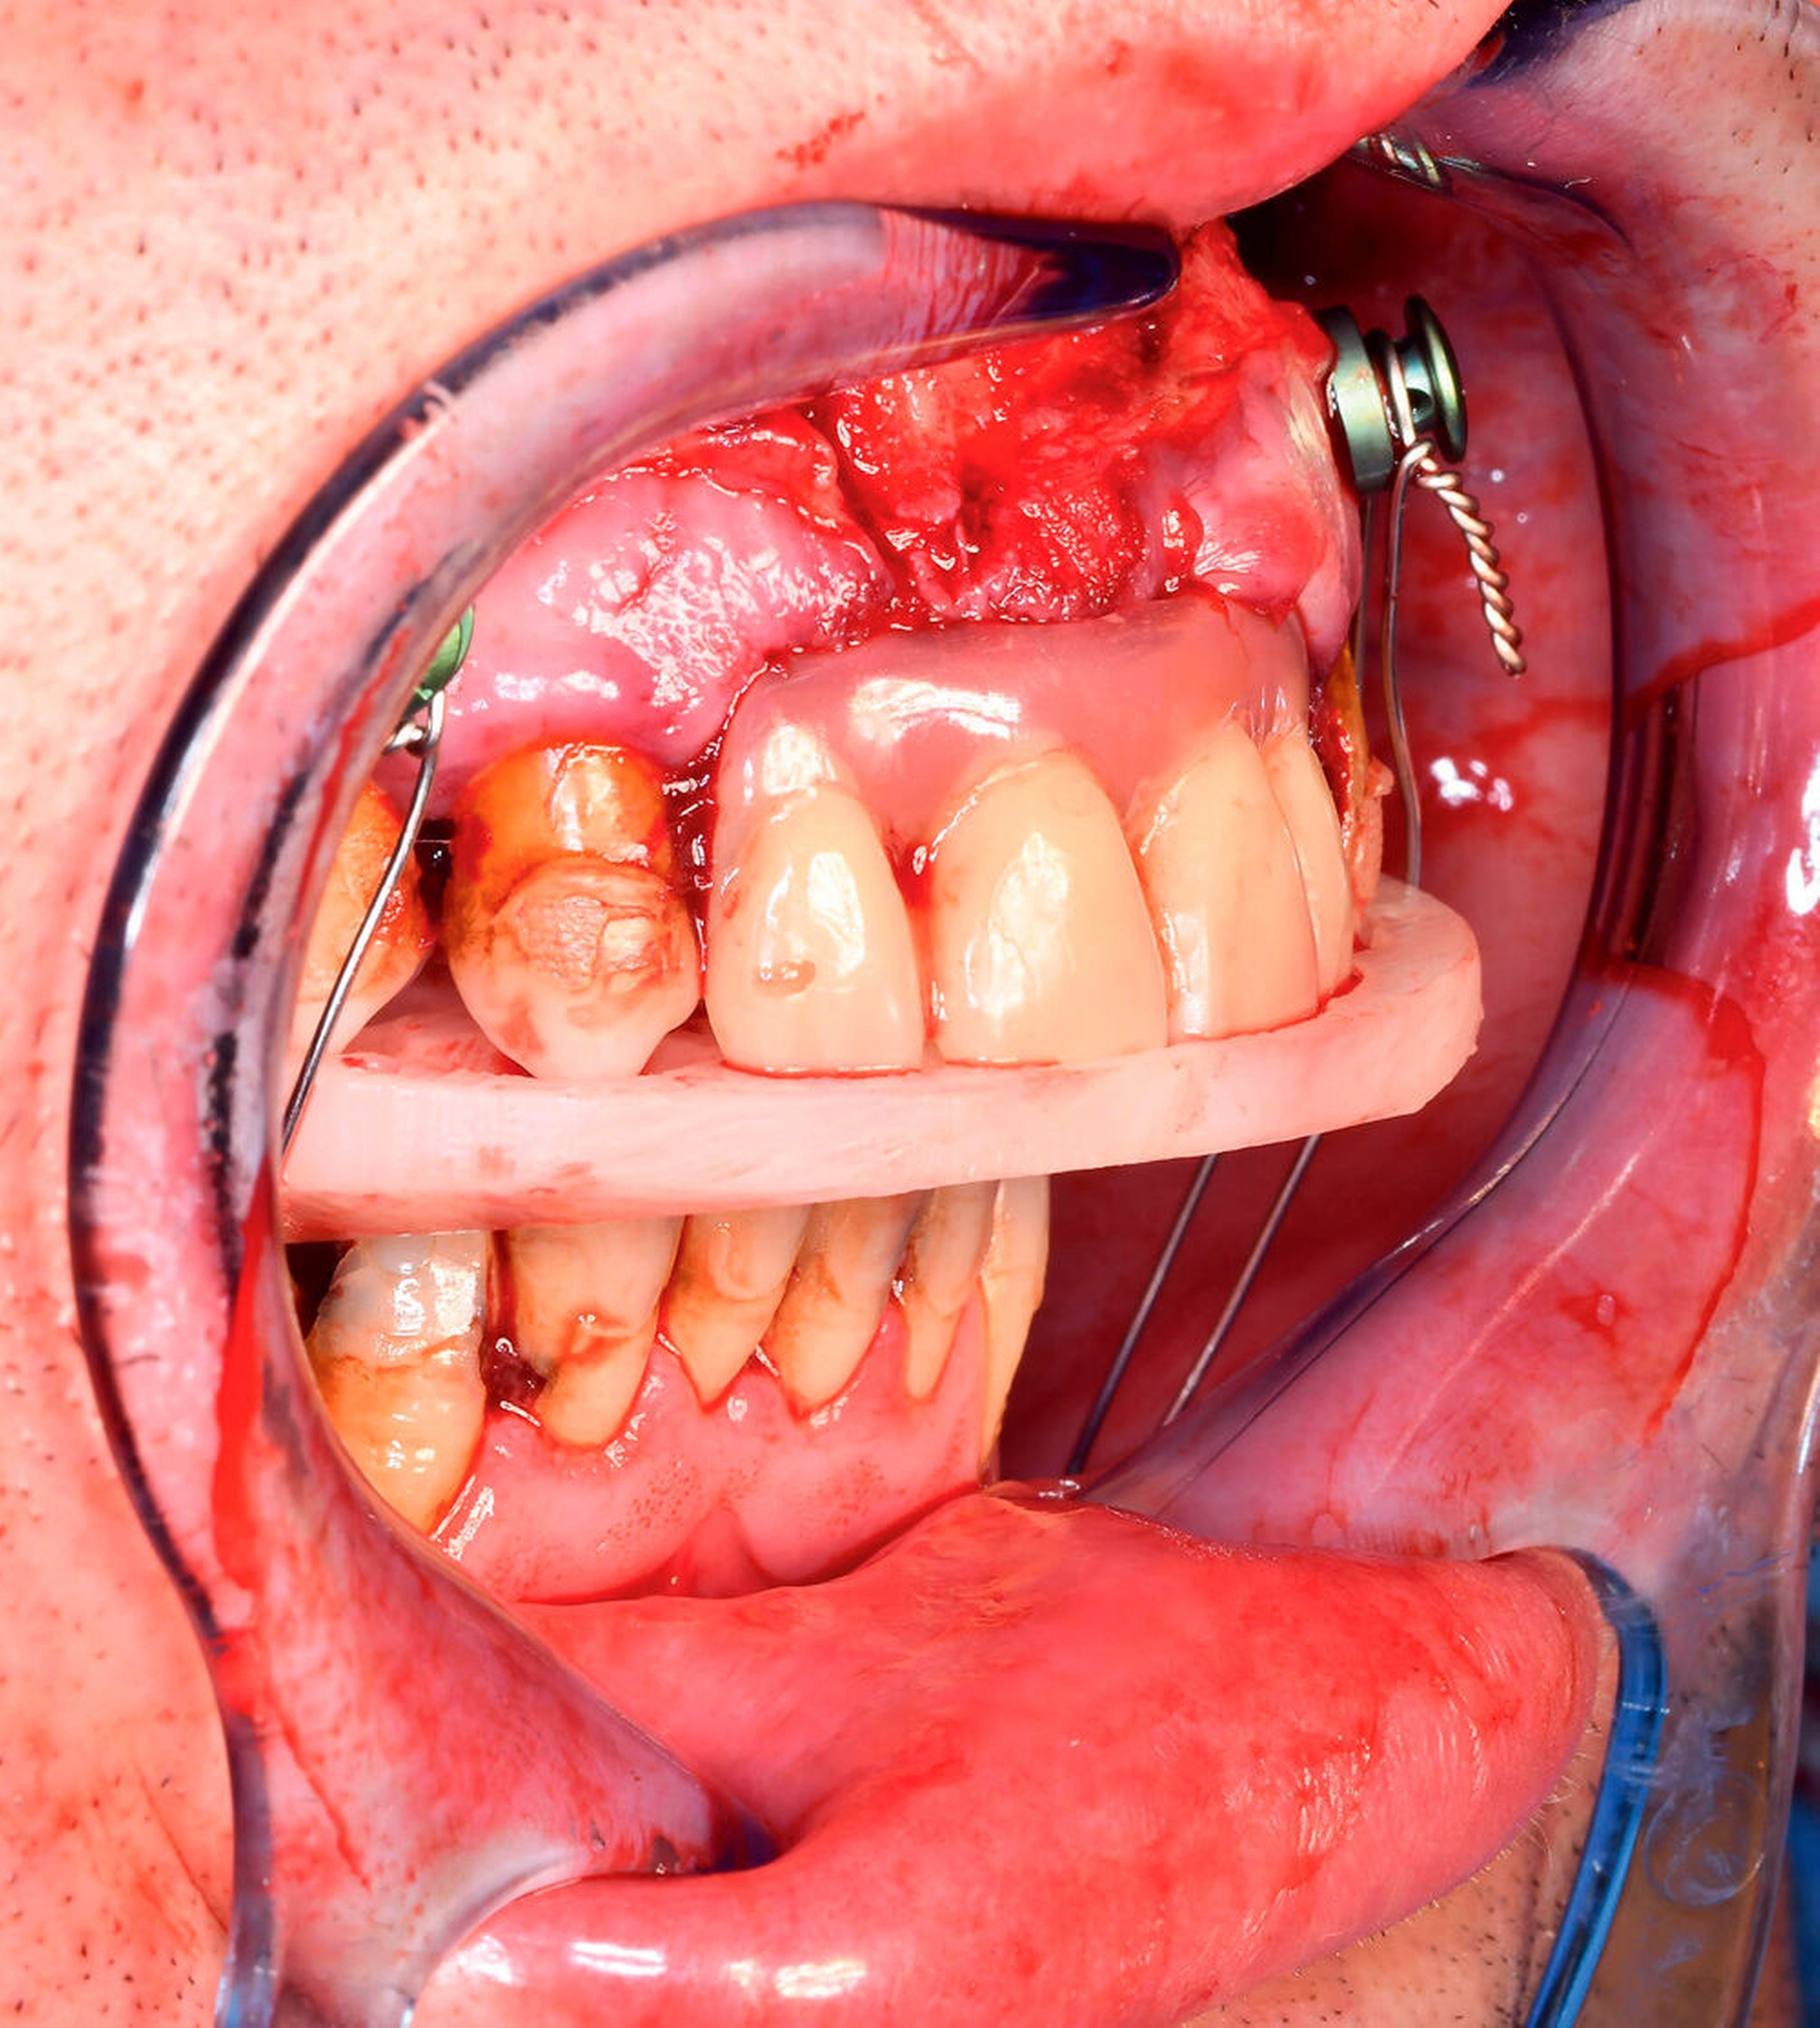

Im August 2019 stellte sich ein 37-jähriger Patient in der ambulanten Sprechstunde der Mund-, Kiefer- und Gesichtschirurgie der Universitätsmedizin Mainz nach Überweisung durch seinen Hauszahnarzt und der Bitte um Therapieübernahme bei notwendiger Zahnsanierung vor. Bei der klinischen Untersuchung zeigte sich eine ausgedehnte Sanierungsbedürftigkeit der Zähne bei skelettaler Klasse II mit 7 mm Distalbisslage und einer mit 1 cm maximalen Schneidekantendistanz (SKD-max.) stark eingeschränkten Mundöffnung (Abbildung 1). Nebenbefundlich litt der auf Unterarmgehstützen angewiesene Patient bei einem Körpergewicht von 120 kg und einer Körpergröße von 170 cm an einer Adipositas per magna (BMI > 40), belastungsabhängiger Dyspnoe und einem obstruktiven Schlafapnoesyndrom bei verkleinertem posteriorem „airway space“, was den Patienten zum Schlafen in aufrechter Position zwang.

Aufgrund der fehlenden Dringlichkeit zur dentalen Sanierung und der Komplexität des Krankheitsbildes erfolgte die Wiedervorstellung des Patienten zur Planung und Erstellung eines interdisziplinären Behandlungskonzepts, das ohne Möglichkeit einer kieferorthopädischen Vor- oder Nachbehandlung aufgrund des geringen Restzahnbestands aus einem kieferchirurgisch-prothetischen Therapieansatz bestand. Grundpfeiler der Therapieplanung und Durchführung bildeten der beidseitige alloplastische Kiefergelenksersatz mittels Patienten-individueller Implantate mit gleichzeitiger Unter- und Oberkiefervorverlagerung sowie die Anfertigung einer Ober- und einer Unterkieferprothese nach Extraktion der nicht erhaltungswürdigen Zähne nach dem Ampelsystem der DGZMK im Sinne des synoptischen Behandlungskonzepts als 3-D-virtuelles „backward planning“. Dabei diente die prothetische Interimsversorgung sowohl der intraoperativen, Splint-gestützten Verschlüsselung der Zielokklusion als auch der postoperativen Okklusionssicherung. Die Planung und laborseitige Herstellung der Zahnprothese erfolgte ausschließlich auf Basis der 3-D-gedruckten Patientenmodelle, da eine suffiziente intraorale Abformung aufgrund der stark eingeschränkten Mundöffnung nicht möglich war (Abbildung 3).

Nach Extraktion der nicht erhaltungswürdigen Zähne 17, 16, 12–27, 36, 46 und 47 und Eingliederung der präformierten Ober- und Unterkiefer-Intermediatprothese folgte die Oberkieferosteotomie in der Le-Fort-I-Ebene mit Neuausrichtung und Osteosynthese unter Verwendung eines CAD/CAM-gefertigten Okklusions-Zwischensplints. Ein zeitgleich gehobener und als Interpositionsosteoplastik eingebrachter kortikospongiöser Knochenspan vom Beckenkamm diente zur Vergrößerung der knöchernen Anlagerungsfläche nach Oberkiefervorverlagerung (Abbildung 4). Die anschließende Darstellung des rechten Kiefergelenks erfolgte über die Extension des präaurikulären Zugangs entlang der vorbestehenden Narbe nach retromandibulär, die Darstellung des linken Kiefergelenks über einen nach parietal extendierten präaurikulären und zusätzlich retromandibulären Zugang.